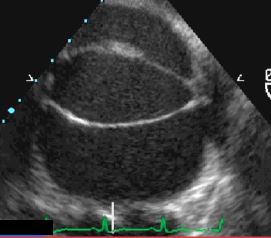

La fermeture spontanée est un évènement assez fréquent dans les CIV de la chambre d’admission, périmembraneuses et musculaires, puisque ceci survient dans 40% des cas [13]. La CIV réalise un shunt G-D non-cyanogène qui surcharge la circulation pulmonaire. Contrairement aux CIV acquises qui sont musculaires, inférieures et apicales, la majorité des CIV congénitales se situent anatomiquement très haut au niveau de la chambre d'admission et de la chambre de chasse des ventricules. Le sang qui emprunte le shunt court-circuite en quelque sorte la cavité ventriculaire droite; le travail de pression et de volume est effectué par le VG, qui est la force propulsive du flux à travers le shunt et à travers les poumons. Le VD est un conduit passif qui n'est mis à contribution et ne s’hypertrophie que lorsque se développe une hypertension pulmonaire. La CIV provoque donc une surcharge de volume pour le VG, qui doit propulser le sang à travers le shunt dans le circuit pulmonaire; ce volume lui revient par l'OG (Vidéo et Figure 15.32). C'est donc en premier lieu une insuffisance gauche qui guette le malade porteur d'une CIV (Figure 15.33) [4].

Vidéo: Hypertrophie dilatative du VG due à la surcharge de volume par la CIV.

Figure 15.32 : Représentation schématique du shunt d'une CIV. Le sang propulsé par le VG à travers la CIV est éjecté dans l’AP, d’où il revient à l’OG et au VG. La surcharge de volume est donc pour le ventricule gauche. Le ventricule droit fonctionne comme un conduit passif et ne s'hypertrophie que lorsque la pression pulmonaire devient élevée.

Figure 15.33 : Surcharge de volume et dilatation du VG en cas de CIV.